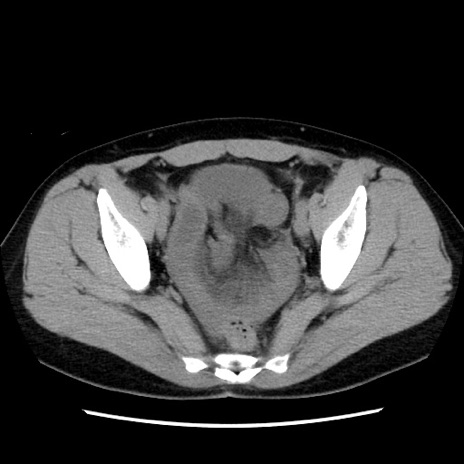

症例10(横断像)

【症例】 50歳代女性

【主訴】 腹痛

【現病歴】前日生レバーを食べた。今朝に排便あり。 昼前に突然発症の腹痛を生じ、当院救急外来を受診した。

【既往歴】 子宮筋腫にてで子宮全摘後

【身体所見】 意識清明、腹部:平坦、軟、下腹部やや左を中心に圧痛・反跳痛あり、筋性防御あり

【データ】WBC 7800、CRP 0.07